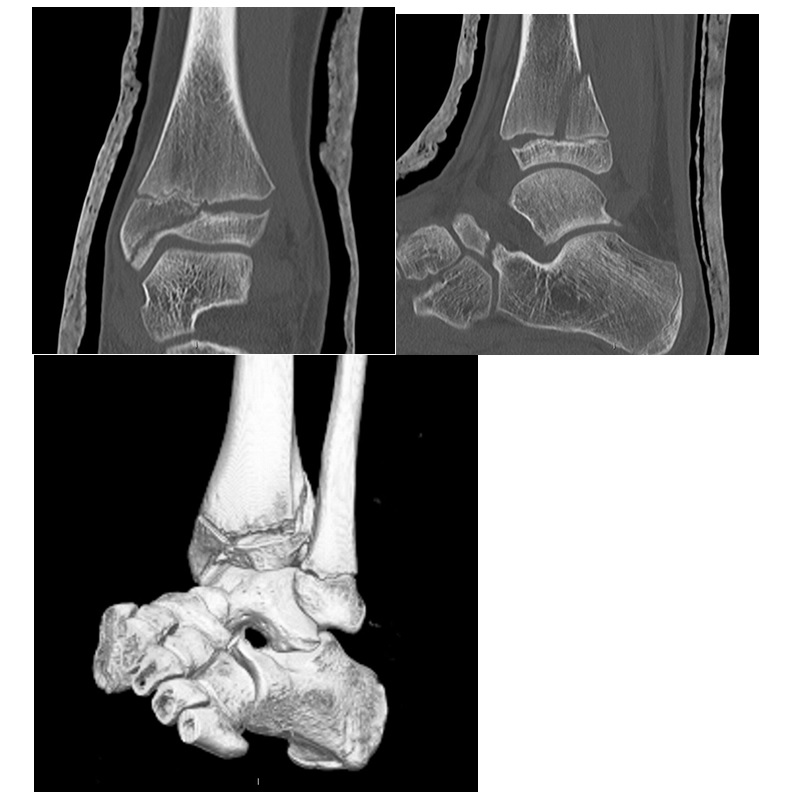

Na obrazie tomografii komputerowej widoczne jest uszkodzenie kości piszczelowej. Jak należy je zakwalifikować?